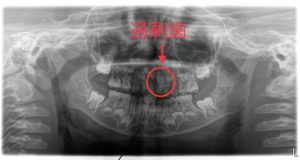

• 歯が多い!?過剰歯とは スタッフブログvol.87

こんにちは!DAの角です。今回は過剰歯についてお話します。 正常な歯の本数とは?みなさん過剰歯という言葉を聞いたことはありますか?過剰歯とは、正常な歯の本数より多く存在する歯です。正常な歯の本数は乳歯が計20本、永久歯は親知らずを...